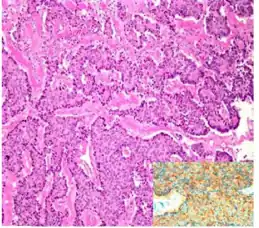

Strumal carcinoid, strongly positive for synaptophysin stain (inset)

The strumal carcinoid is a type of monodermal teratoma with histomorphologic features of (1) the thyroid gland and (2) a neuroendocrine tumour (carcinoid).[1][2]